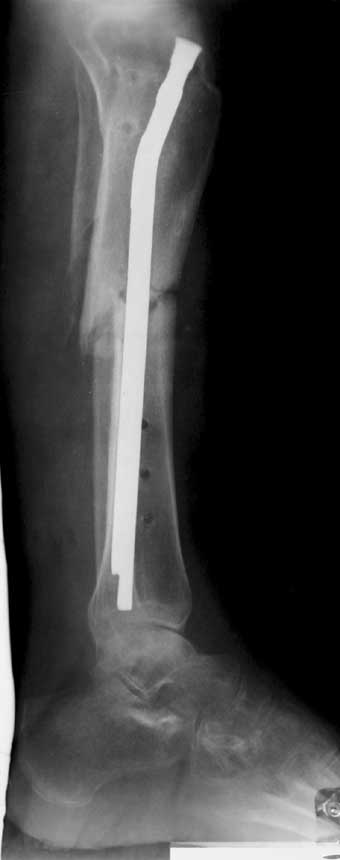

С места аварии в районную больницу, где произвели ампутацию правой голени. Дальше в клинику спец. помощи, где на левой голени были удалены нежизнеспосбные инфицированные отломки, (дефект 13 см) и наложен аппарат Гофмана. Детали неизвестны. Со слов больного, инфекционный процесс левой голени купирован не был. В феврале аппарат был снят и произведен остеосинтез гвоздем (before1;2). В мае, объективно: В нижней трети голени функционирует свищ, отделяемое гнойное: золотистый стафилокок, чувствительный к большинству антибиотиков.

1 июня произведено удаление гвоздя, дренаж костномозгового канала, остеосинтез аппаратом Илизарова ( after 1; 2).